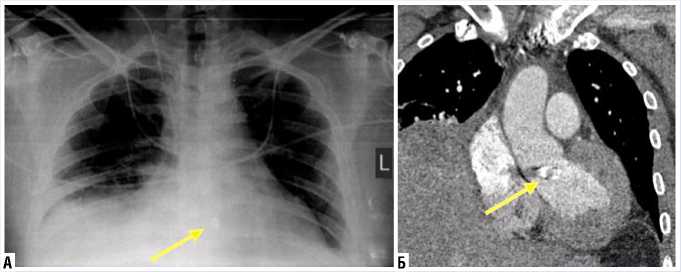

При ЧП ЭхоКГ лоцировано место нахождения инородного тела: верхняя треть МЖП, под правой коронарной створкой аортального клапана (Рис. 3).

Рис. 3. ЧП ЭхоКГ: инородное тело в верхней трети МЖП, под правой коронарной створкой аортального клапана (стрелка).